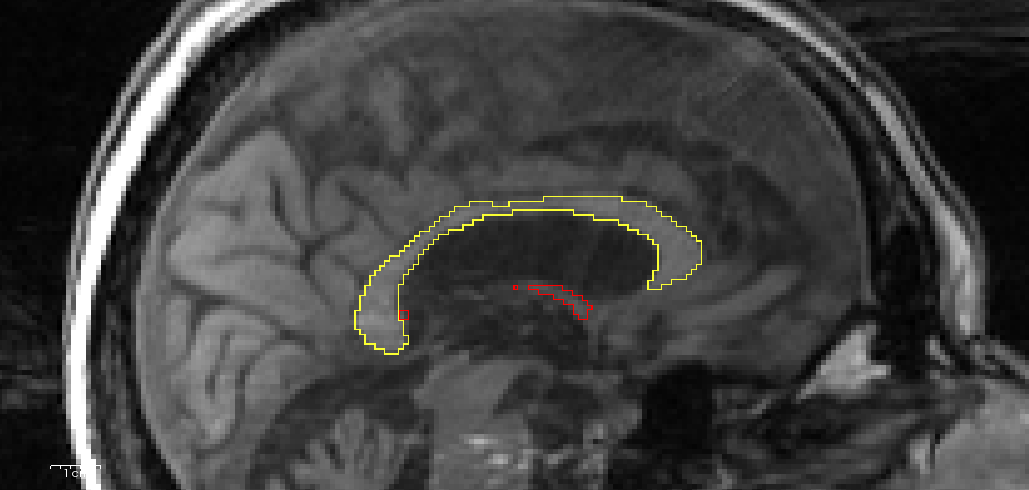

In Figure A.2, we show examples from the difficult test set along with the rater annotation and network output. In case A the contrast of corpus callosum and surroundings is low (note that we use standardized automated contrast adjustment by freeview for all figures). In case B strong artifacts are present (see image background for a clear view of ringing artifacts). In cases B, C, and D, the corpus callosum is thin and deformed, making segmentation challenging.

Original Image

Rater Annotation

Network Prediction

A

B

C

D